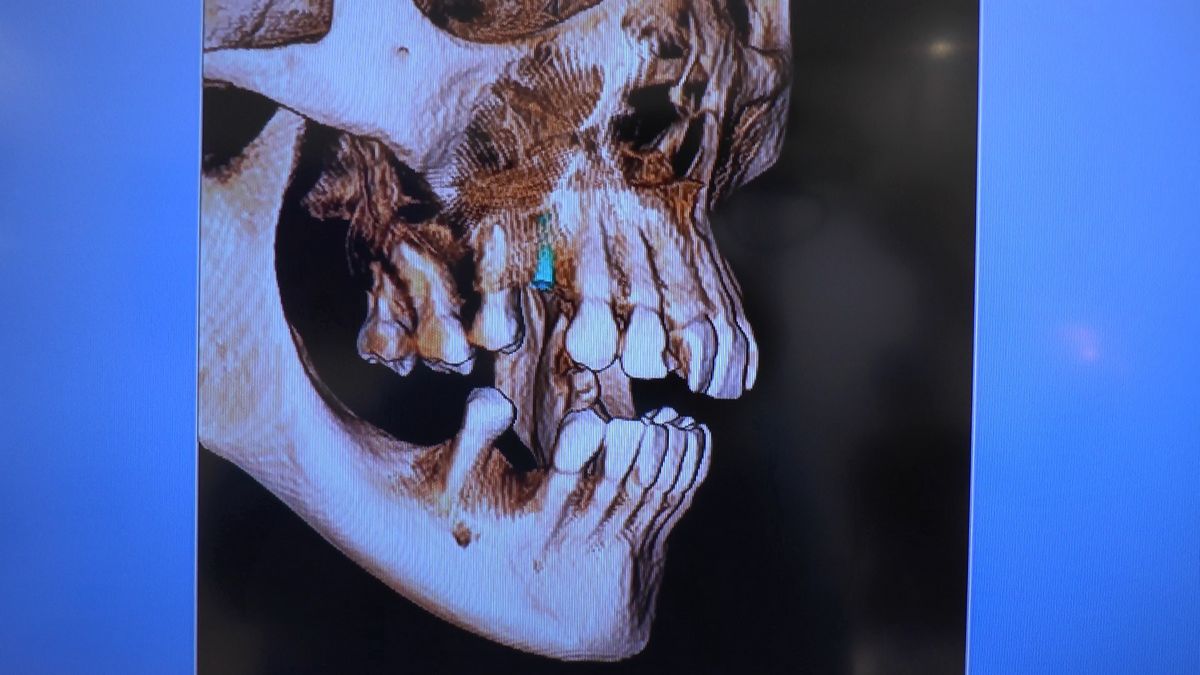

W ostatni weekend czerwca 2018 roku kursanci II Sezonu Preludium Implantologii odbyli piątą, finałową sesję, która w całości podporządkowana była praktyce. W ciągu dwóch dni zabiegowych Lekarze uczestniczący w szkoleniu przeprowadzili szereg zabiegów pod kierunkiem dr n.med. Violetty Szycik. Wszczepili 17 implantów oraz przeprowadzili ekstrakcje i zabiegi regeneracyjne kości. Zabiegi były wykonywane także w sedacji dożylnej z udziałem specjalisty anestezjologii i intensywnej terapii dr Jolanty Grzybowskiej. Preludium implantologii to nowy program edukacyjny dla adeptów implantologii stomatologicznej, którego celem jest wprowadzenie do implantologii poprzez pozyskanie wiedzy w szerokim zakresie i uwzględnieniem szczegółów mających decydujące znaczenie dla powodzenia leczenia implantologicznego. Ale tak jak wszystkie szkolenia w Instytucie Vivadental, w tym wiodące Practiculum Implantologii, zorientowane jest na praktyce i samodzielnym wykonywaniu zabiegów pod kierunkiem Mentora. To najlepsza edukacja w medycynie zabiegowej, a zarazem najlepszy start do implantologii.